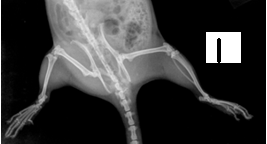

Photographs. 1, 2, 3 are of Anti-arthritic activity of Effect of Petroleum ether and Methanol extract of leaf of Pergularia daemia [Forsk]

Radiographic Analysis

On the 21st day immediately after measurement of paw volume displacement and recording of secondary lesions, the one rat from each group was animals were sacrificed by cervical dislocation and carotid bleeding and subjected to the radiological examination using Agfa digital System and Seimens X ray machine. These radiographs were evaluated for any deformity especially for soft tissue swelling and bone erosion, joint space narrowing by independent qualified person. [21]

Radiographic analysis is considered to be the best tool to screen the any drug in this regard. In present study radiographic analysis of the joint showed significant prevention in progress of joint [20, 21]. By synthetic therapy, there is rapid reduction in inflammation in arthritis is observed with corticosteroids but the effect of these drugs were for short time. Corticosteroids become less effective over time where as arthritis is usually active for years together [22]. From the above research work, the leaf extract of Pergularia daemia [Forsk] is a good substitute for corticosteroids therapy for arthritis.